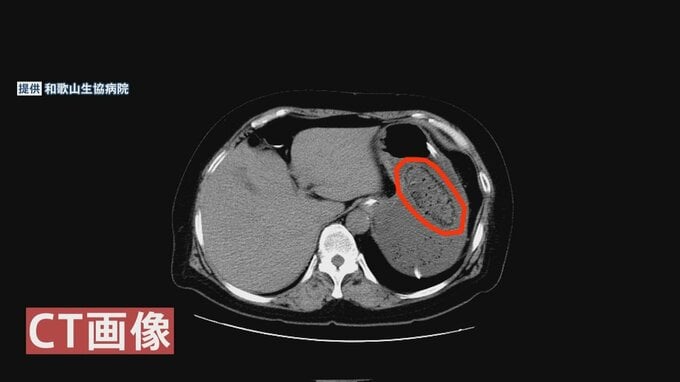

「1日10個以上は食べてました。毎日のように。病院に入る手前で意識がなくなった。先生が後日に写真見せてくれて、胃に1つ、わりと大きな石ができていたと教えてくれた」

「柿の渋みですね。その主成分である『シブオール』というものが胃の中で酸とかと合わさることによって、周りの食物繊維とかを巻き込んで石になるといわれています。小腸から取り出したのは大体4センチ強の石でした。食べた後に(数年かけて)、徐々にというよりは比較的早く石になるようです」